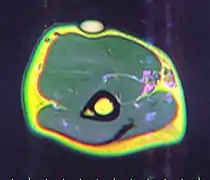

MRI showing lipoma of the arm

A physical exam is typically the easiest way to diagnose it. Rarely, a tissue biopsy or imaging may be required. The imaging modality of choice is magnetic resonance imaging (MRI) because it has superior sensitivity of distinguishing it from liposarcoma as well as mapping the surrounding anatomy.[22]